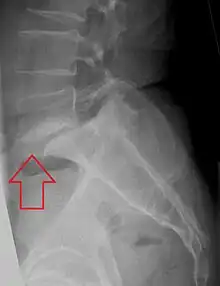

- X-ray of a grade 4 anterolisthesis at L5-S1 with spinal misalignment indicated